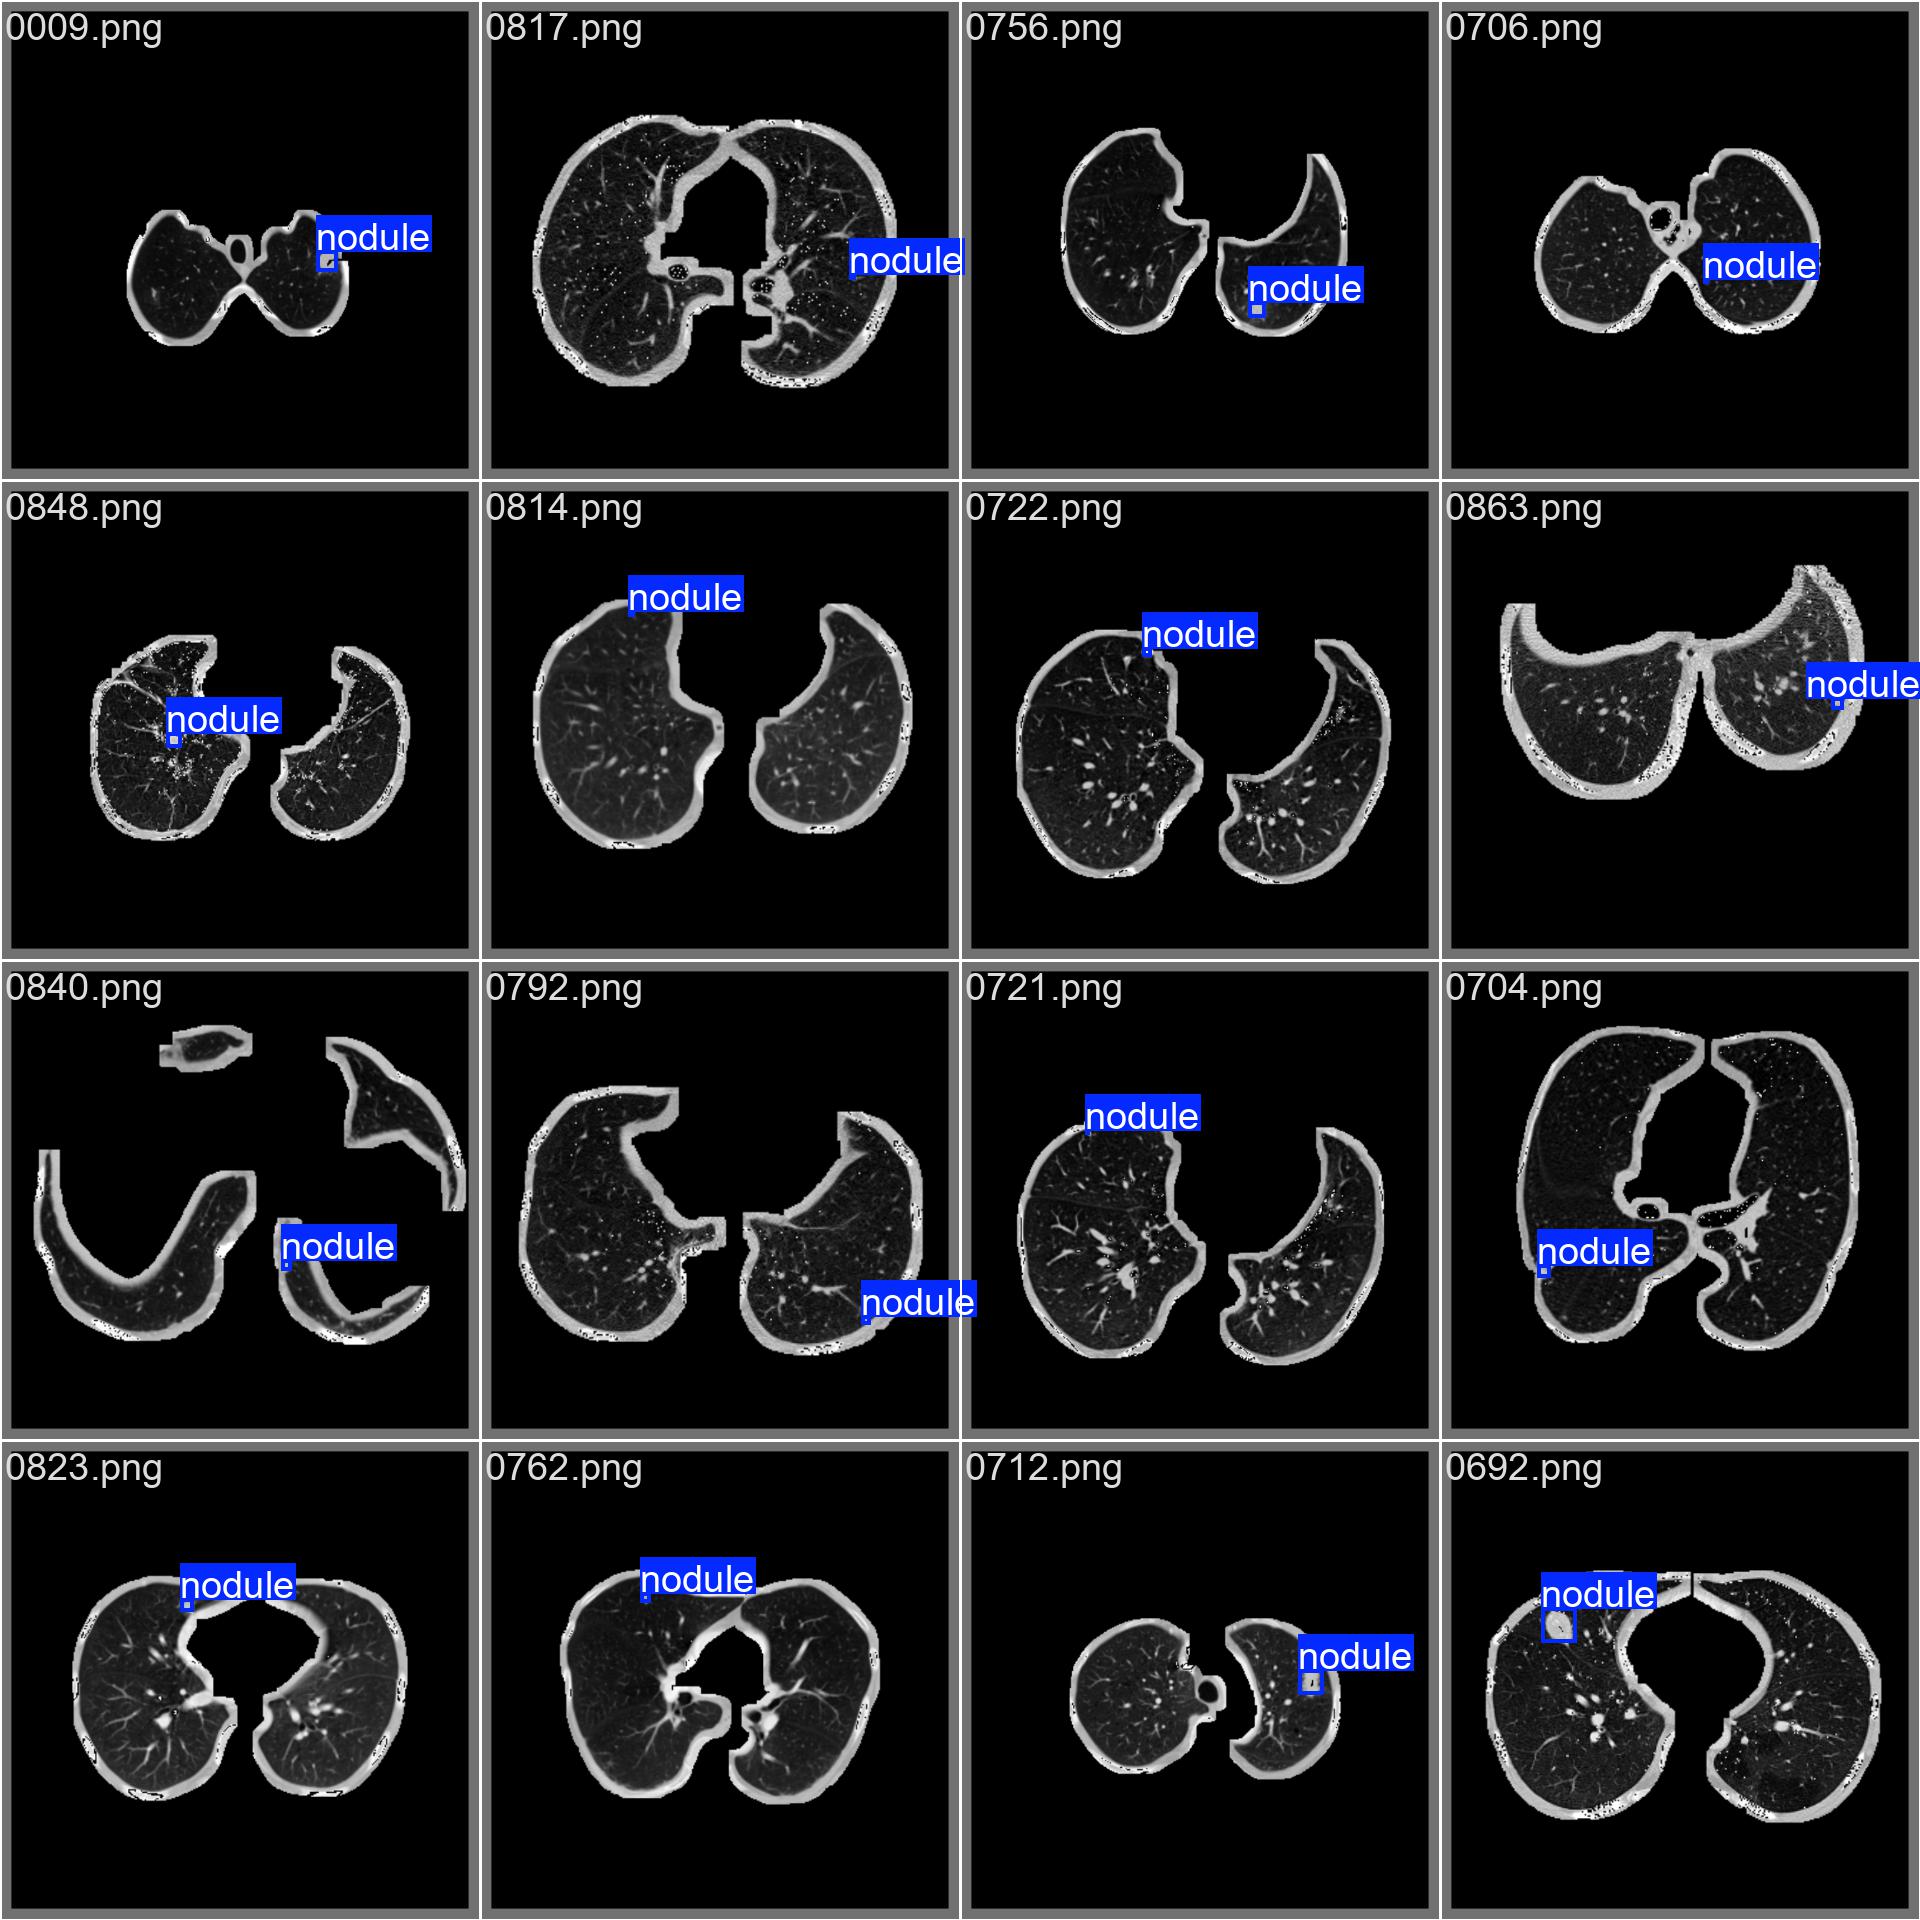

下面是数据集的部分示例。

当iou阈值为0.5的时候,模型在测试集上的map可以达到68.1%。下面是一个预测图像,可以看出,我们的模型可以有效的预测出这些尺度比较小的交通目标。